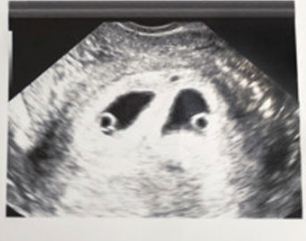

طريقة علمية لتشخيص الحمل بتوأم

لا يمكن الكشف عن الحمل في توأم إلا عن طريق الموجات فوق الصوتية. تعتبر الموجات فوق الصوتية من أفضل الطرق لتشخيص الحمل ، ويتم إجراؤها عادةً في بداية الثلث الثاني من الحمل. بمجرد تشخيص العديد من الولدان على الموجات فوق الصوتية ، يمكن للأطباء تحديد ما إذا كانوا متطابقين أم لا.